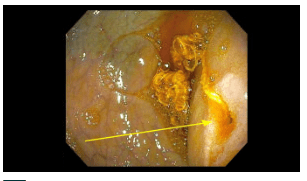

Due to the obstruction which was thought to be anatomic, the GI service deferred management to pediatric surgery. The surgical service requested GI inspection with endoscopy immediately prior to surgery. If a bezoar was identified, the surgical plan was for a mini-laparotomy. If not, the surgical plan was for laparoscopy repair.

Endoscopy findings: There was a narrowed opening (different orientation of same narrowing in both pictures) with a string-like material.

Surgical findings: A duodenal web with a piece of lint was identified. The patient had a laparoscopic wedge excision with a transverse closure of the duodenotomy. The lint may have occluded the tiny opening of the web that he had been living with since he was born.

My take: This is the first time I have seen the endoscopic appearance of a duodenal web.